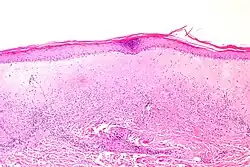

Histologie eines atrophen Lichen sclerosus. -

Histologie eines hypertrophen Lichen sclerosus.